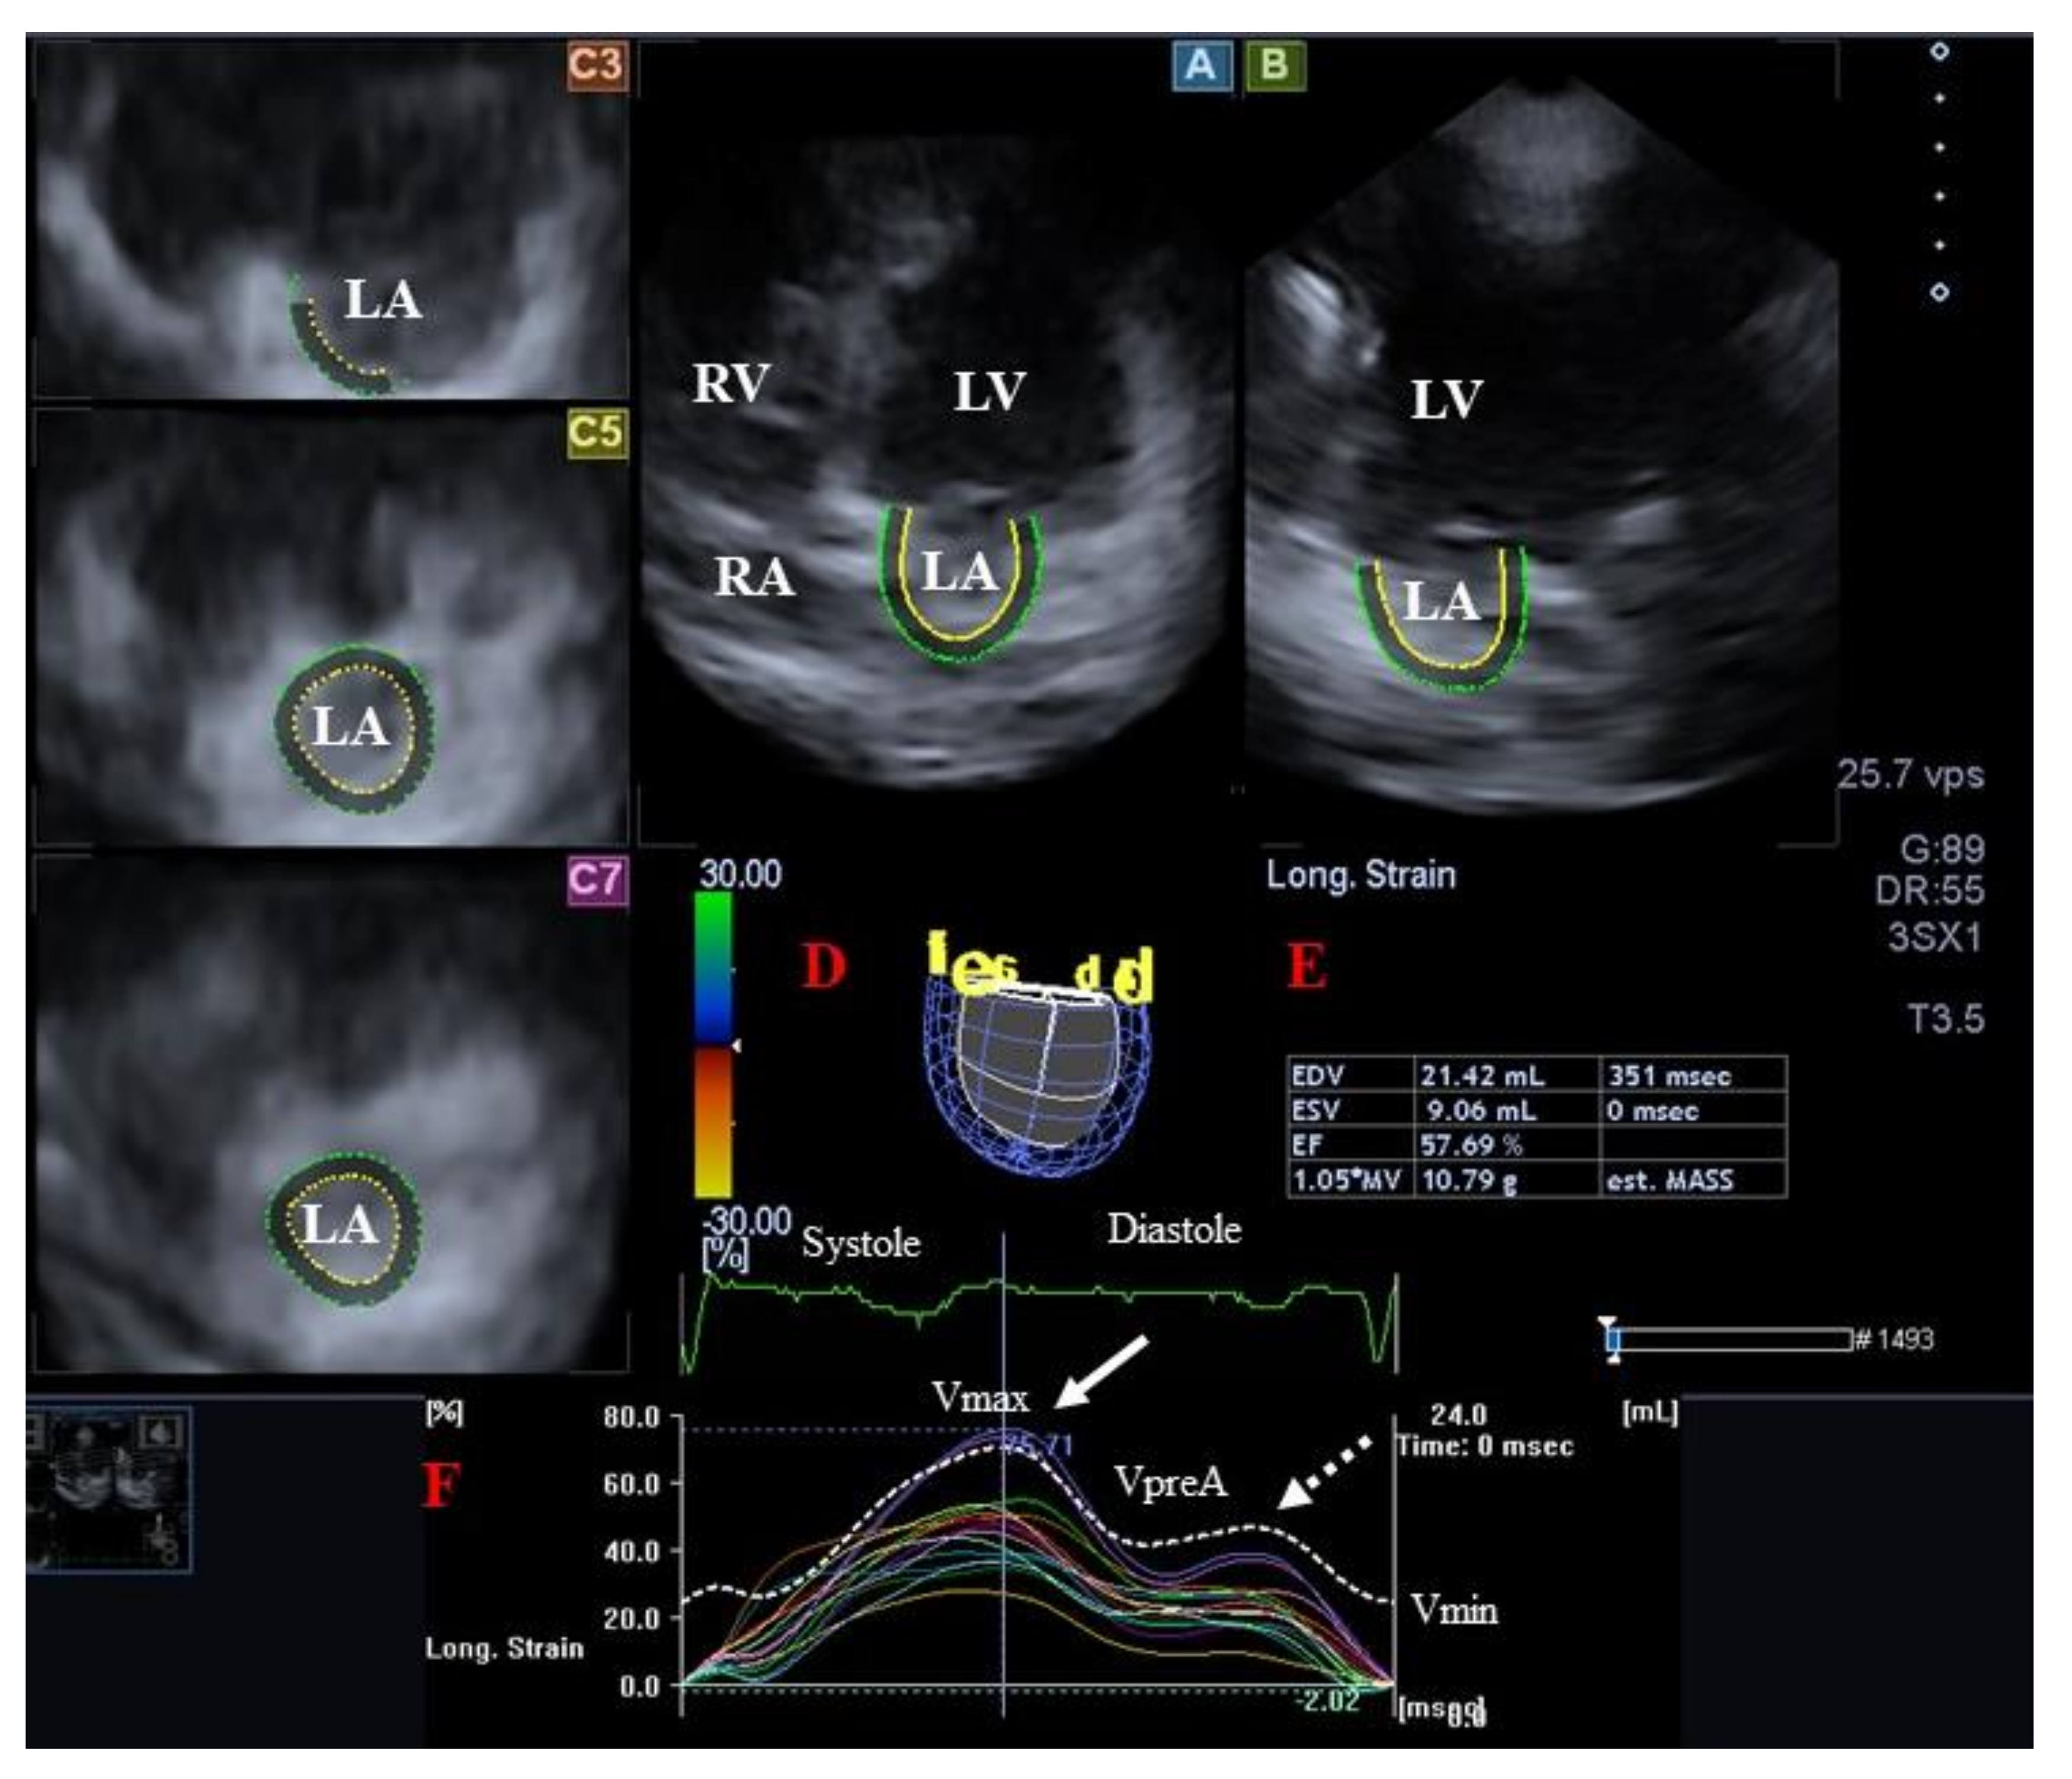

- Kormányos, Á.; Domsik, P.; Kalapos, A.; Valkusz, Z.; Lengyel, C.; Forster, T.; Nemes, A. Three-dimensional speckle tracking echocardiography-derived left atrial deformation analysis in acromegaly (Results from the MAGYAR-Path Study). Echocardiography 2018, 35, 975–984. [Google Scholar] [CrossRef]